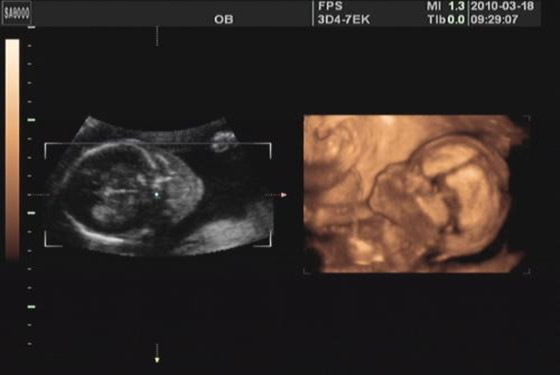

怀孕的4-6个月为孕中期,进入孕中期以后孕妈咪会感觉身体状态越来越好,此时的胃口也已经大开,之前的种种厌食、没胃口的迹象也已经消失不见了,大多数孕妈咪已经慢慢可以感觉到胎儿的胎动了(初次怀孕的孕妇感觉胎动可能没那么早),这个时候想必你一定很关心胎儿长成什么样子了,是不是发育正常等问题,有这些疑问是很正常的,怀孕以后女性本身就有些敏感,只要是关乎到胎儿发育成长的问题她们就不会错过,为了大家能够弄清楚这些事情,我们可以通过怀孕四个月的胎儿B超图来进行了解学习。

怀孕第四个月也就是孕13-16周,胎儿差不多有母亲手掌般大小,在这几周里胎儿的发育成长是比较迅速的,这个月胎儿大多五官(耳朵、鼻子、眼睛、嘴巴)已经发育成形,胎盘也相对发育成熟了,怀孕的4-7个月是胎儿和母体相对稳定的时期,也就是说孕妈咪和胎儿宝宝在这几个月里是相当的舒坦,妈咪可以“随心所欲”的吃吃喝喝,再也不用受呕吐的困扰,胎儿宝宝可以在妈咪腹中“自由流动”,想怎么玩就怎么玩,等过了这几个月孕妇肚子越来越大,胎儿宝宝个头越来越大时一切都没有那么随便了。